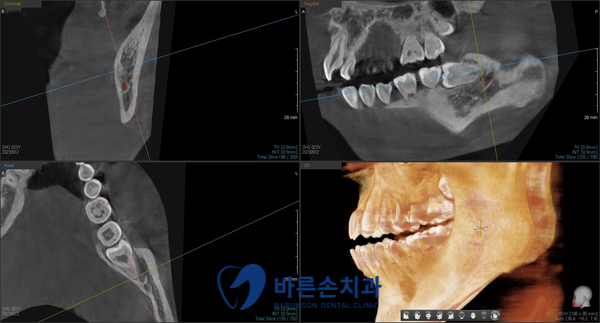

안녕하세요. <의정부 바른손치과>입니다.! 오늘은 사랑니 발치 증례를 보여드리도록 하겠습니다. 이 환자분은 20대 중반의 남성분으로 양쪽 아래 사랑니가 아프셔서 발치를 하러 저희 바른손치과를 찾아주셨습니다. 엑스레이 사진에서 보시면 양쪽 위 아래 사랑니가 모두 있고 왼쪽 아래 사랑니가 누워서 부분적으로 매복되어 있는 상태입니다. 구강 내 사진입니다. 좌우 모두 사랑니 머리가 일부만 구강내로 맹출해있습니다. 이런 경우 음식물이 끼기 쉽고, 칫솔로 제거도 쉽지가 않습니다. 그래서, 잇몸이 부어 피가 나고 아픈 경우가 자주 일어 날 수 있고 나아가 앞에 있는 치아 까지 썩게 할 수 있습니다ㅜㅜ 이런 경우엔 사랑니 발치를 통해 구강 환경 개선을 해야합니다!!! 사랑니 발치에 앞서 3D CT 촬영을 하였습니다. 사랑니의 형태와 위치, 아래턱뼈에 있는 하치조신경관의 해부학적 위치를 정확히 확인 후 발치에 들어갑니다. 오른쪽 아래 사랑니를 발치하고 엑스레이를 찍어 확인하였습니다. 왼쪽아래 옆으로 누워있는 사랑니도 발치를 하였습니다. 환자분께서는 문제를 일으키던 사랑니를 뽑으니 홀가분하고 시원하다고 하셨습니다.!! 약 일주일 정도 회복기간을 가지시면 사랑니 부위의 잇몸은 어느정도 아물게 됩니다. 사랑니 발치 더이상 두려워 하지 마시고 <의정부 바른손치과>에서 뽑으세요^^ |